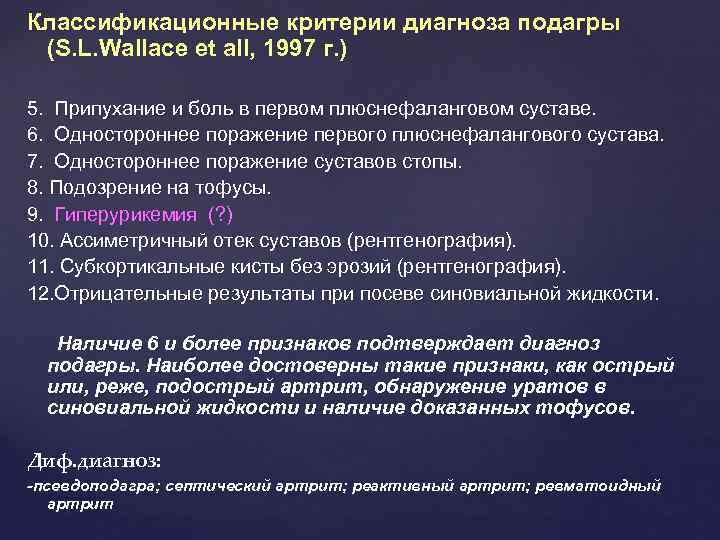

Классификационные критерии диагноза подагры (S. L. Wallace et all, 1997 г. ) А. Наличие характерных кристаллических уратов в суставной жидкости. В. Присутствие тофусов (доказанных), содержащих кристаллические ураты, подтвержденных химически или поляризационной микроскопией. С. Наличие любых 6 из 12 ниже перечисленных признаков: 1. Более одной атаки острого артрита в анамнезе. 2. Воспаление сустава достигает максимума в первый день болезни. 3. Моноартрит. 4. Гиперемия кожи над пораженным суставом.

Классификационные критерии диагноза подагры (S. L. Wallace et all, 1997 г. ) А. Наличие характерных кристаллических уратов в суставной жидкости. В. Присутствие тофусов (доказанных), содержащих кристаллические ураты, подтвержденных химически или поляризационной микроскопией. С. Наличие любых 6 из 12 ниже перечисленных признаков: 1. Более одной атаки острого артрита в анамнезе. 2. Воспаление сустава достигает максимума в первый день болезни. 3. Моноартрит. 4. Гиперемия кожи над пораженным суставом.

Классификационные критерии диагноза подагры (S. L. Wallace et all, 1997 г. ) 5. Припухание и боль в первом плюснефаланговом суставе. 6. Одностороннее поражение первого плюснефалангового сустава. 7. Одностороннее поражение суставов стопы. 8. Подозрение на тофусы. 9. Гиперурикемия (? ) 10. Ассиметричный отек суставов (рентгенография). 11. Субкортикальные кисты без эрозий (рентгенография). 12. Отрицательные результаты при посеве синовиальной жидкости. Наличие 6 и более признаков подтверждает диагноз подагры. Наиболее достоверны такие признаки, как острый или, реже, подострый артрит, обнаружение уратов в синовиальной жидкости и наличие доказанных тофусов. Диф. диагноз: -псевдоподагра; септический артрит; реактивный артрит; ревматоидный артрит

Классификационные критерии диагноза подагры (S. L. Wallace et all, 1997 г. ) 5. Припухание и боль в первом плюснефаланговом суставе. 6. Одностороннее поражение первого плюснефалангового сустава. 7. Одностороннее поражение суставов стопы. 8. Подозрение на тофусы. 9. Гиперурикемия (? ) 10. Ассиметричный отек суставов (рентгенография). 11. Субкортикальные кисты без эрозий (рентгенография). 12. Отрицательные результаты при посеве синовиальной жидкости. Наличие 6 и более признаков подтверждает диагноз подагры. Наиболее достоверны такие признаки, как острый или, реже, подострый артрит, обнаружение уратов в синовиальной жидкости и наличие доказанных тофусов. Диф. диагноз: -псевдоподагра; септический артрит; реактивный артрит; ревматоидный артрит